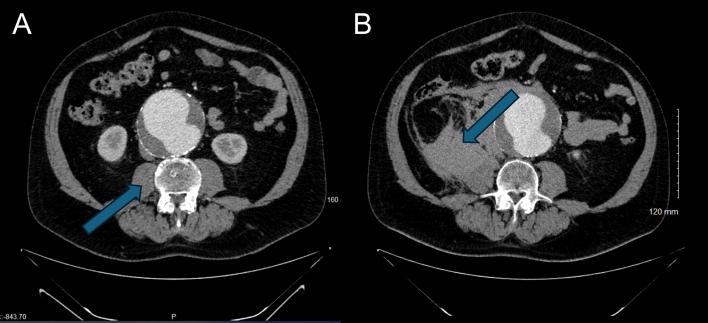

图 1 A 和 B:对比增强轴向计算机断层扫描图像

A 图为破裂前初始 CT 扫描:显示大型肾下型动脉瘤,瘤壁完整;B 图为患者动脉瘤破裂后病情恶化的后续扫描:显示右侧新发腹膜后血肿,对右侧腰大肌产生占位效应,符合破裂表现。A 图中箭头指向右侧腰大肌,B 图中箭头指向破裂性腹主动脉瘤所致血肿。

患者从CT室返回急诊科后,主诉睾丸疼痛急性加重,血流动力学不稳定,血压降至 60/30mmHg,但双侧股动脉搏动仍可触及。其他生命体征为:心率55次/分钟,室内空气下血氧饱和度95%。患者出现嗜睡、意识模糊,情况危急。医院立即启动复苏措施,并将患者送回CT室紧急复查。复查影像显示动脉瘤囊右侧出现新发腹膜后出血(分别见图1A与图1B、图2A与图2B对比)。患者被直接转运至急诊手术室,启动大量输血方案,并通知手术室工作人员、麻醉团队及高级外科医师。本次诊断的主要挑战是从孤立性睾丸疼痛中识别出症状性腹主动脉瘤。

图 2 A 和 B:对比增强轴向计算机断层扫描的更远端视图

睾丸疼痛是急诊科常见的泌尿系统疾病特征性症状,如睾丸扭转、附睾炎、鞘膜积液或尿路结石等。关于症状性腹主动脉瘤患者出现孤立性睾丸疼痛的病因,一种假说认为是动脉瘤囊刺激生殖股神经所致,血肿或局部出血可能进一步压迫神经。生殖股神经起源于腰丛 L1/L2 节段,沿腹后壁下行,经腰大肌前表面,随后分为生殖支和股支。生殖支负责阴囊的感觉传导,并支配提睾肌。本例患者的横断面CT影像显示,右侧腰大肌被血肿浸润(图 1B、图 2B)。故推测动脉瘤囊或血肿的局部刺激可能引发睾丸牵涉痛。主动脉通常位于腹部中线左侧,因此症状性腹主动脉瘤患者的睾丸疼痛非典型表现更常见于左侧,这也使得本病例的非典型性更为显著。尽管该假说仍为推测,但影像中腰大肌区域受累及其与生殖股神经的邻近关系支持这一解释。生殖股神经痛相关研究也为该疼痛的解剖学基础提供了佐证——生殖股神经痛是指因生殖股神经受压或损伤引发的神经病理性疼痛,症状包括阴囊疼痛。然而,大多数关于生殖股神经痛的文献聚焦于医源性损伤,而非血管压迫。